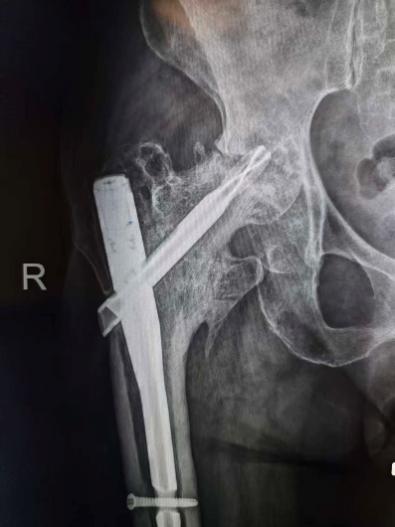

此次入院前X线片及CT

怀着最后一线希望,谈大妈与家属慕名来到陕西省核工业二一五医院创伤骨科寻求诊治。吴超副主任医师接诊后,立即为谈大妈安排了详细且全面的检查,经影像检查发现,虽然粗隆间骨折已愈合,但此前植入的部分内固定物竟突破了股骨头、侵入髋臼,导致股骨头已坏死变形、髋臼骨质缺损。

“这是内固定术后严重的并发症,如不及时干预,患者将永久丧失行走功能。”王争刚主任医师一针见血地告诉家属。